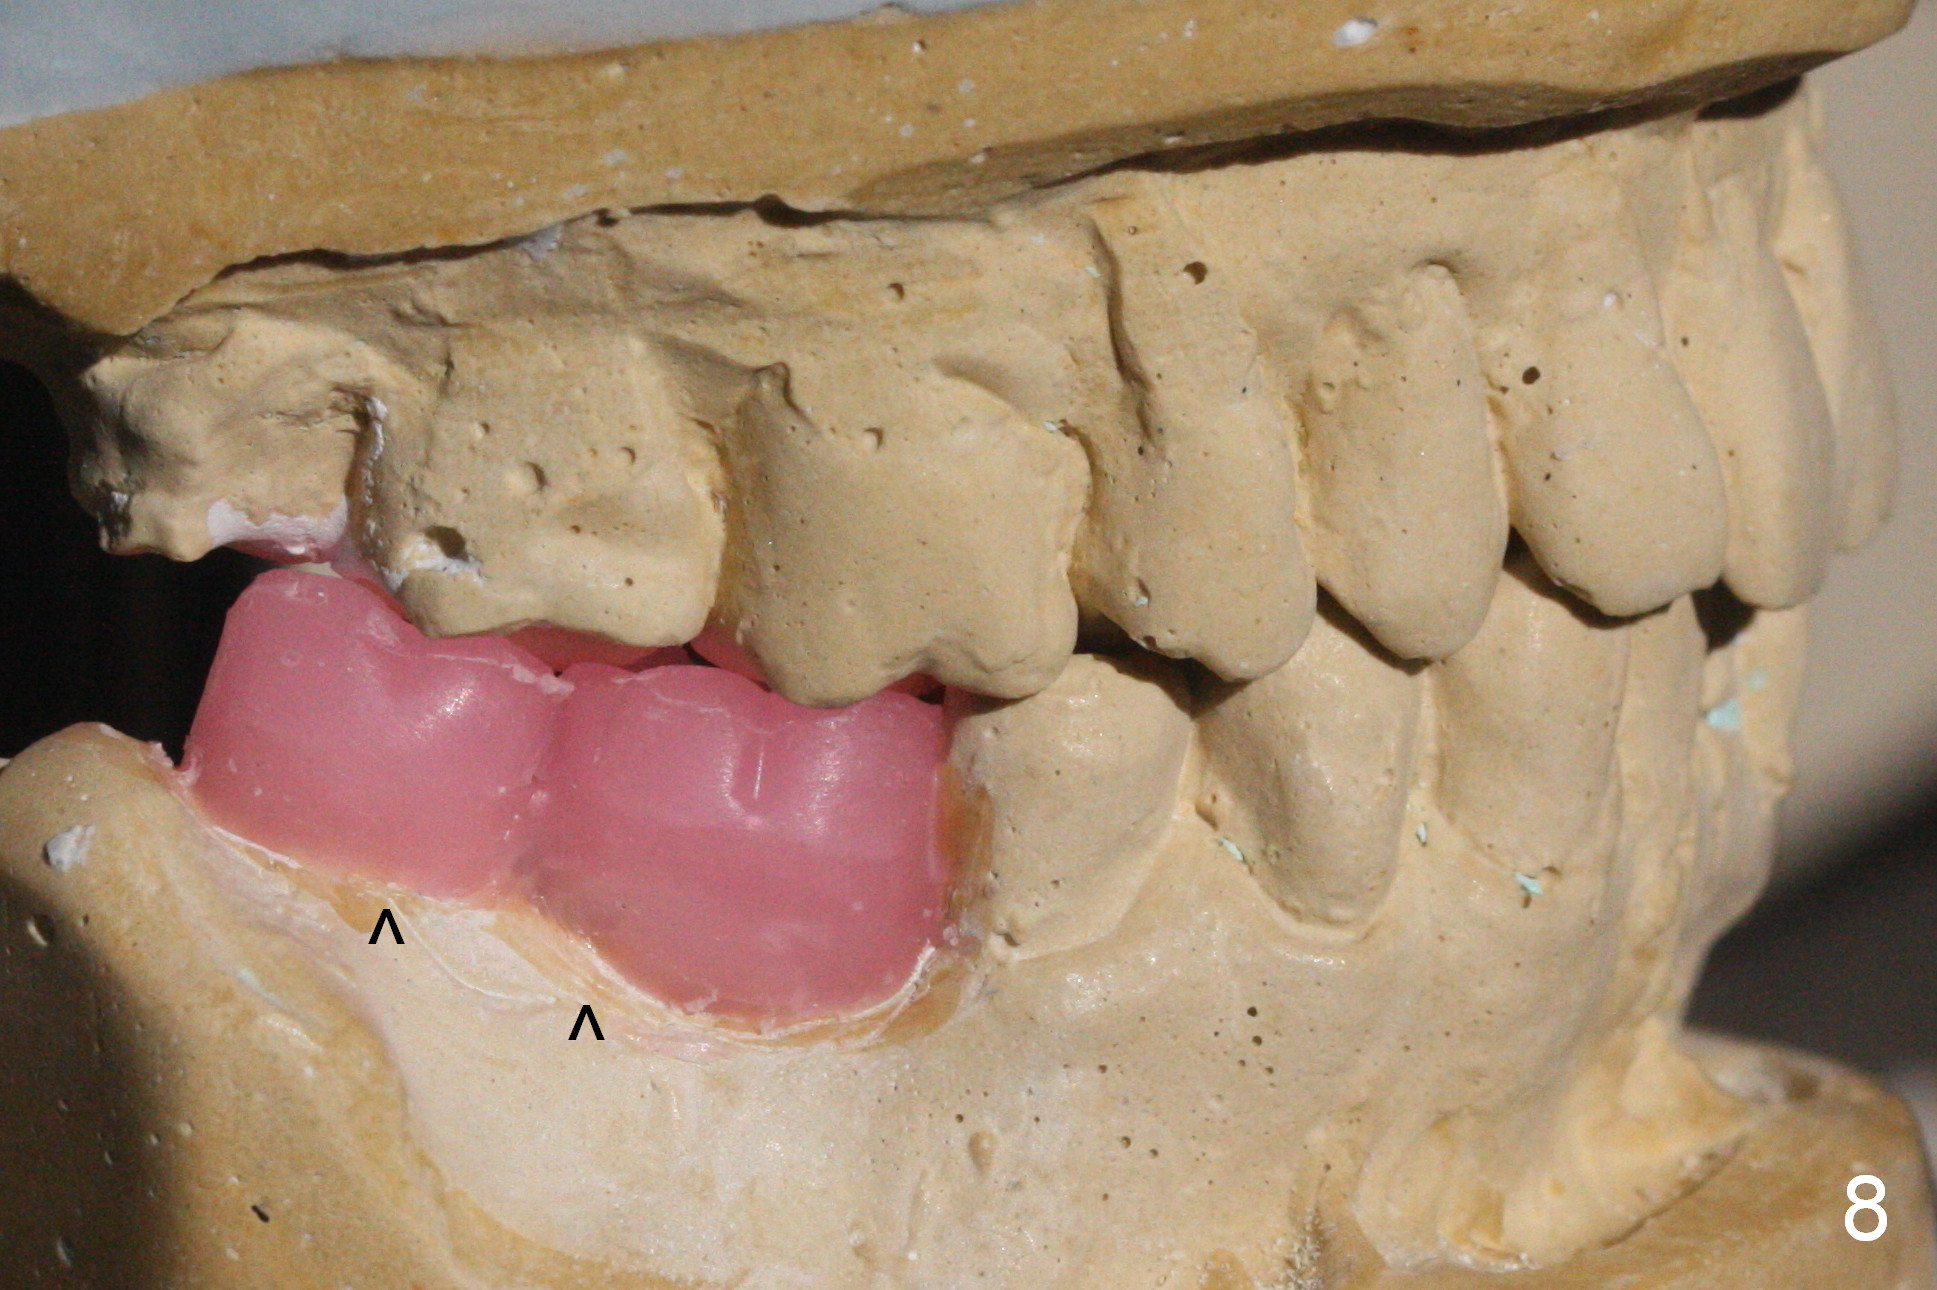

One of the patient's daughter feels that the treatment is too complicated. She would like to have the 2nd molars extracted and implants at the 1st and 2nd molar sites (from Fig.5,6 to 7-9). Since the upper canines are missing (Fig.5,6), the final occlusion will be Class II posteriorly (Fig.8,9).